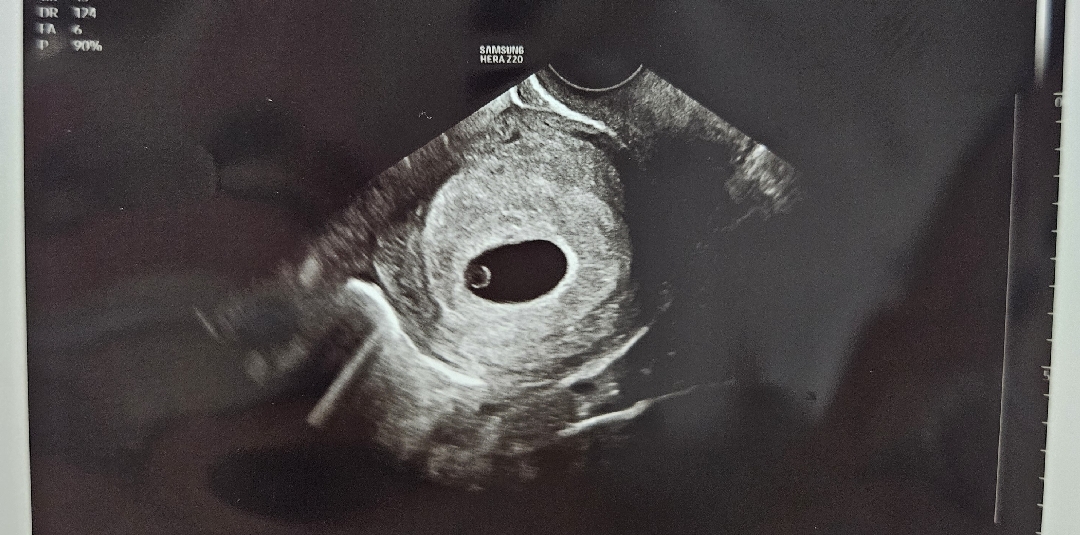

5주6일차 첫 초음파 사진이에영

난황, 애기집까지 보고왔어용. 심장소리는 잘 안들린다고 못들어서 너무 아쉽네용 난황, 애기집 괜찮아보이나요??